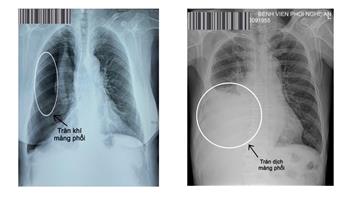

Tràn dịch và tràn khí màng phổi là hai bệnh lý nguy hiểm, cần phải nhập viện cấp cứu. Nếu không được phát hiện và xử trí kịp thời có thể dẫn đến tử vong.... [ Xem thêm ]